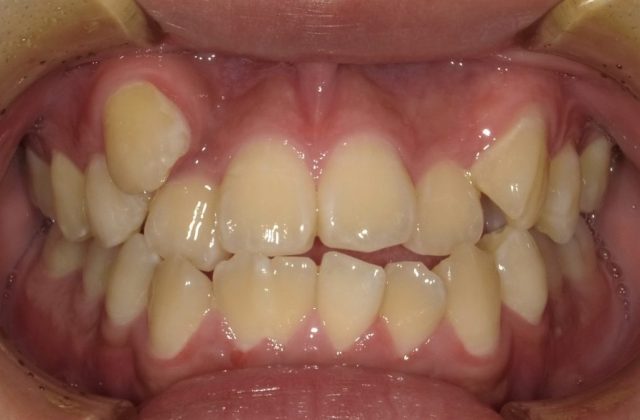

【正面観】

2023年1月

【before ⇨ after】

| 主訴 | 前歯のガタガタ |

| 診断名 | 前歯部叢生を伴う下顎前突 |

| 初診時年齢・性別 | 7歳10ヶ月・男児 |

| 治療期間 | 1段階目:2年3ヶ月 経過観察:6年 2段階目:1年5ヶ月~ |

| 治療方法・治療内容 | 4本抜歯・フルブラケット・ストレートワイヤーテクニック |

| 費用 | 1段階目検査診断料¥315,00 1段階目矯正基本料¥315,000、調整料¥113,400 経過観察料¥11,000 2段階目検査診断料¥5,500 2段階目矯正基本料¥440,000 調整料¥121,000~ |

| デメリット・注意点 | 抜歯が必要・硬い物や大きい物など食事への配慮 |